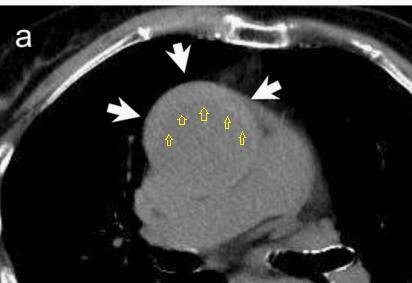

下图的胸部CT平扫,有什么致命的问题?

图7

仔细一看,主动脉里面有线样阴影!并且,线样阴影两边的密度一高一低!

图8

增强CT一看,主动脉夹层,密度相对高的是流动的血液!

图9